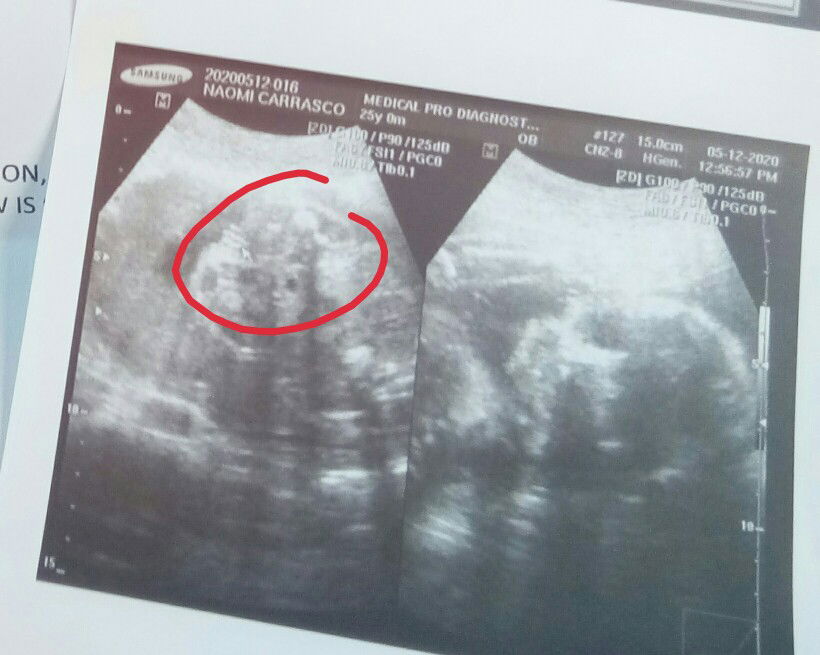

GIRL TALAGA?

MGA SIS BAKA MAY NKAKAALAM TUMINGIN DYAN IF SURE BA NA GIRL SI BABY? YAN NASA CURSOR MAY RED NA BILOG, YUNG PARANG TATLO GUHIT DAW IS PEMPEM NI BBY?